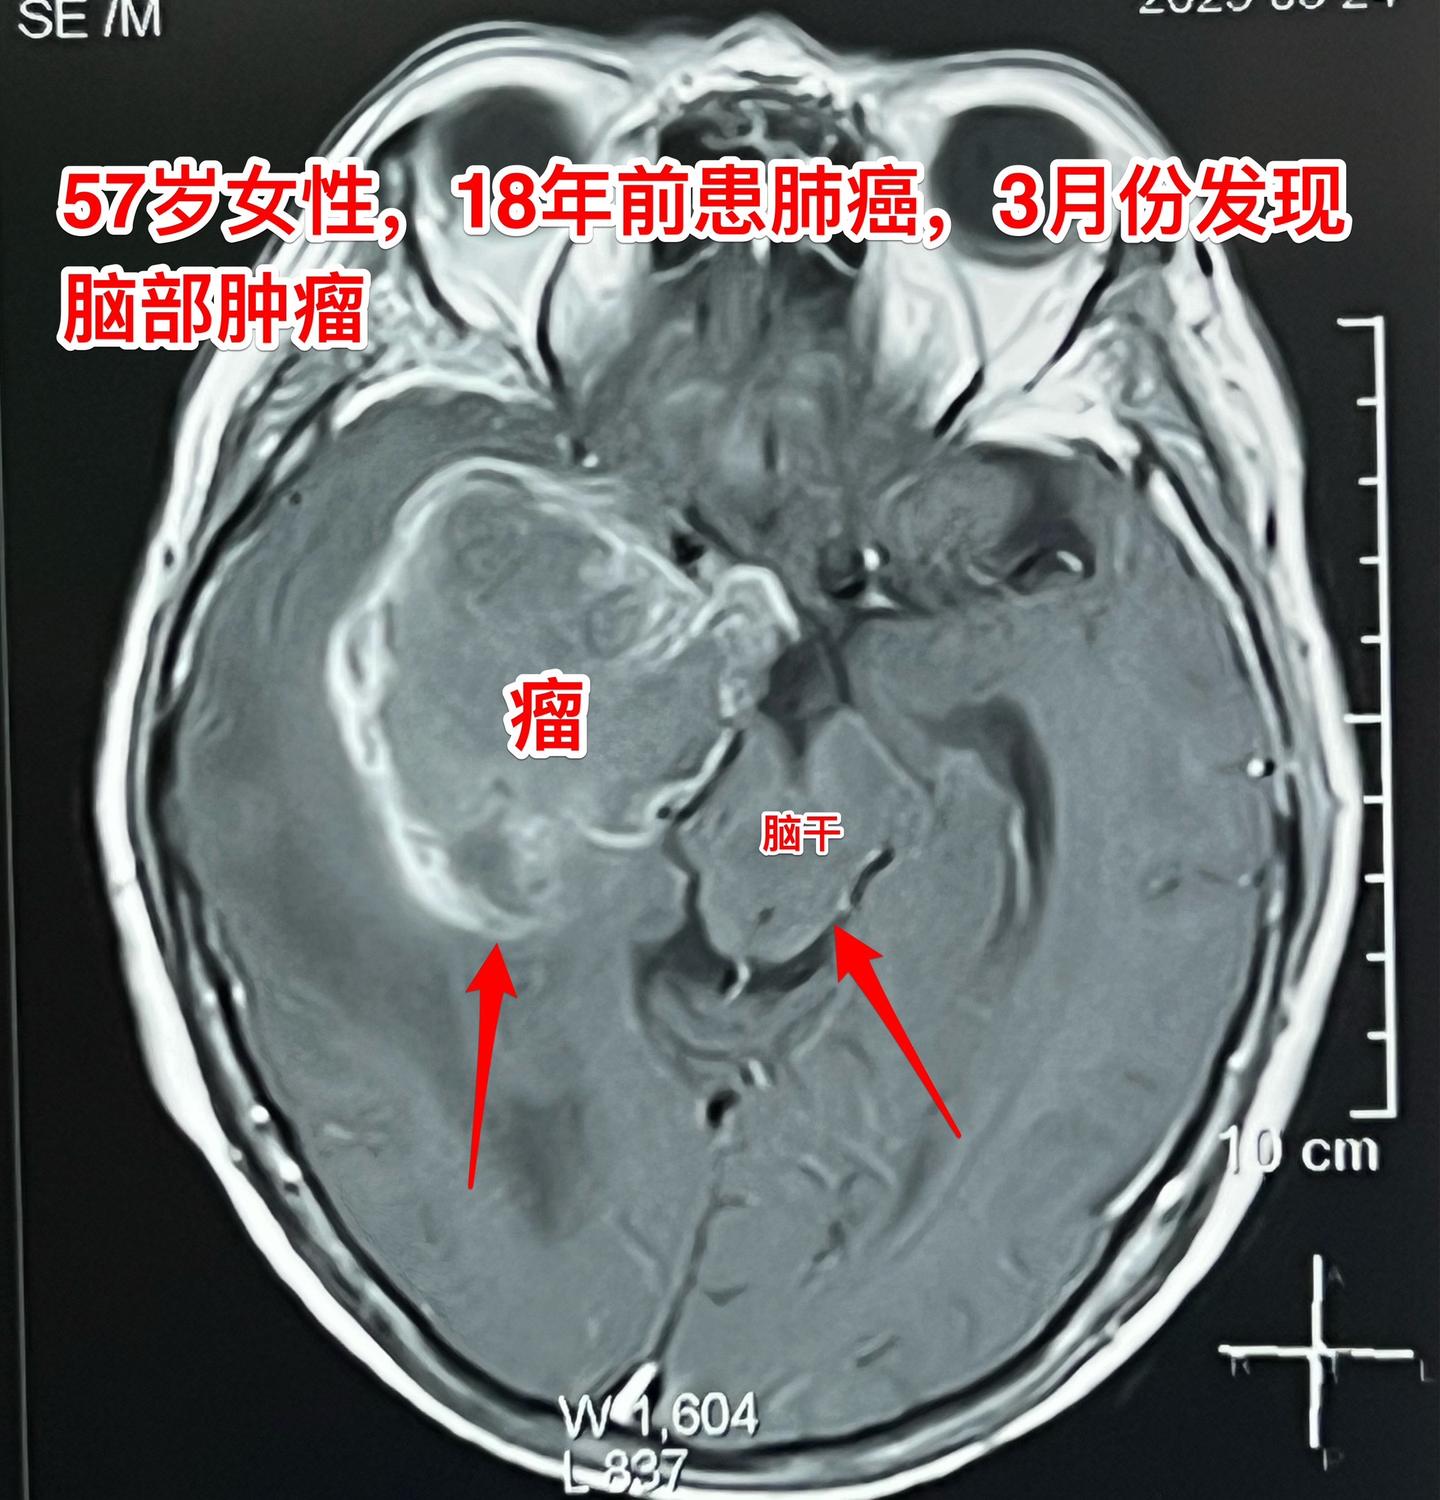

肺癌患者多年后出现脑部转移。57岁的韶关女病人在18年前患肺癌,作了手术切除肺癌并作了化疗,随后多次复查,没有发现肿瘤复发。她也在正常上班。 就在这个春节前她的婆婆去世了,她的情绪似乎受到严重影响,和平时不一样,总是担惊受怕。 三月份经家人提醒,到当地医院去作头部CT检查,结果发现脑部有个瘤,像鸡蛋那么大了!医生怀疑是胶质瘤。 3月22日到北京来找我住院。3月27日晚作了手术,手术中看见肿瘤形态符合肺癌脑转移。等待病理报告。